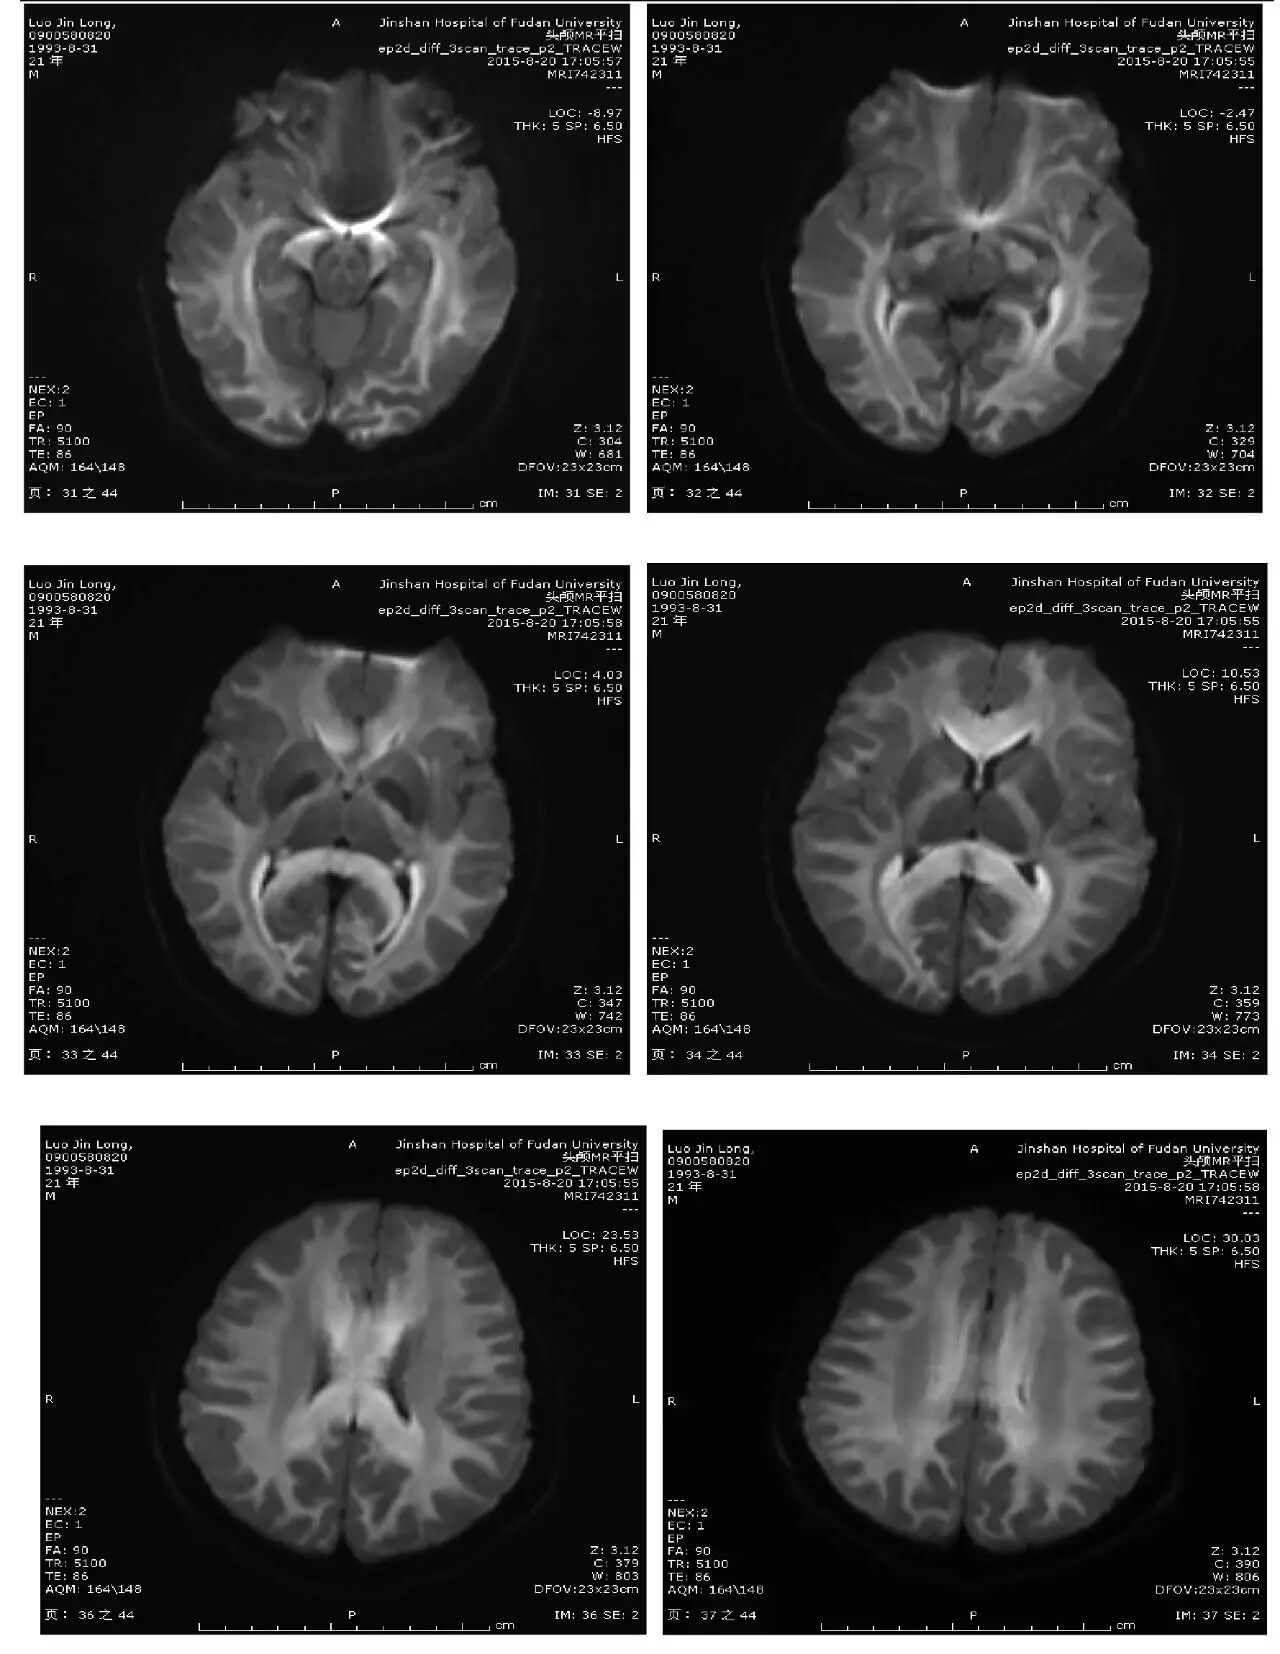

主诉:头痛、反应迟钝、口齿不清4天

现病史:头中线部位钝痛,反应迟钝,口齿不清,无发热,无恶心、呕吐,无饮水呛咳,四肢乏力。无麻木不适。2天后出现视物模糊。外院头颅CT:两侧大脑半球低密度灶。

(点击查看高清图)